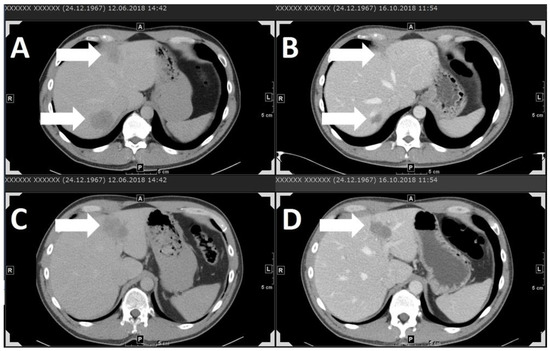

| Case series HD, 2019 (unpublished) | retrospective, monocentre, stage-IV UM | pembro: 12 nivo: 1 ipi + nivo: 7 total: 20 | 55% | pembro 2 mg/kg Q3W nivo 3 mg/kg Q2W ipi 3 mg/kg + nivo 1 mg/kg Q3W, followed by nivo 3 mg/kg Q2W | PR | 11.8% | 2.85 | 29.4% | 5.9% | 2.75 | 30% |